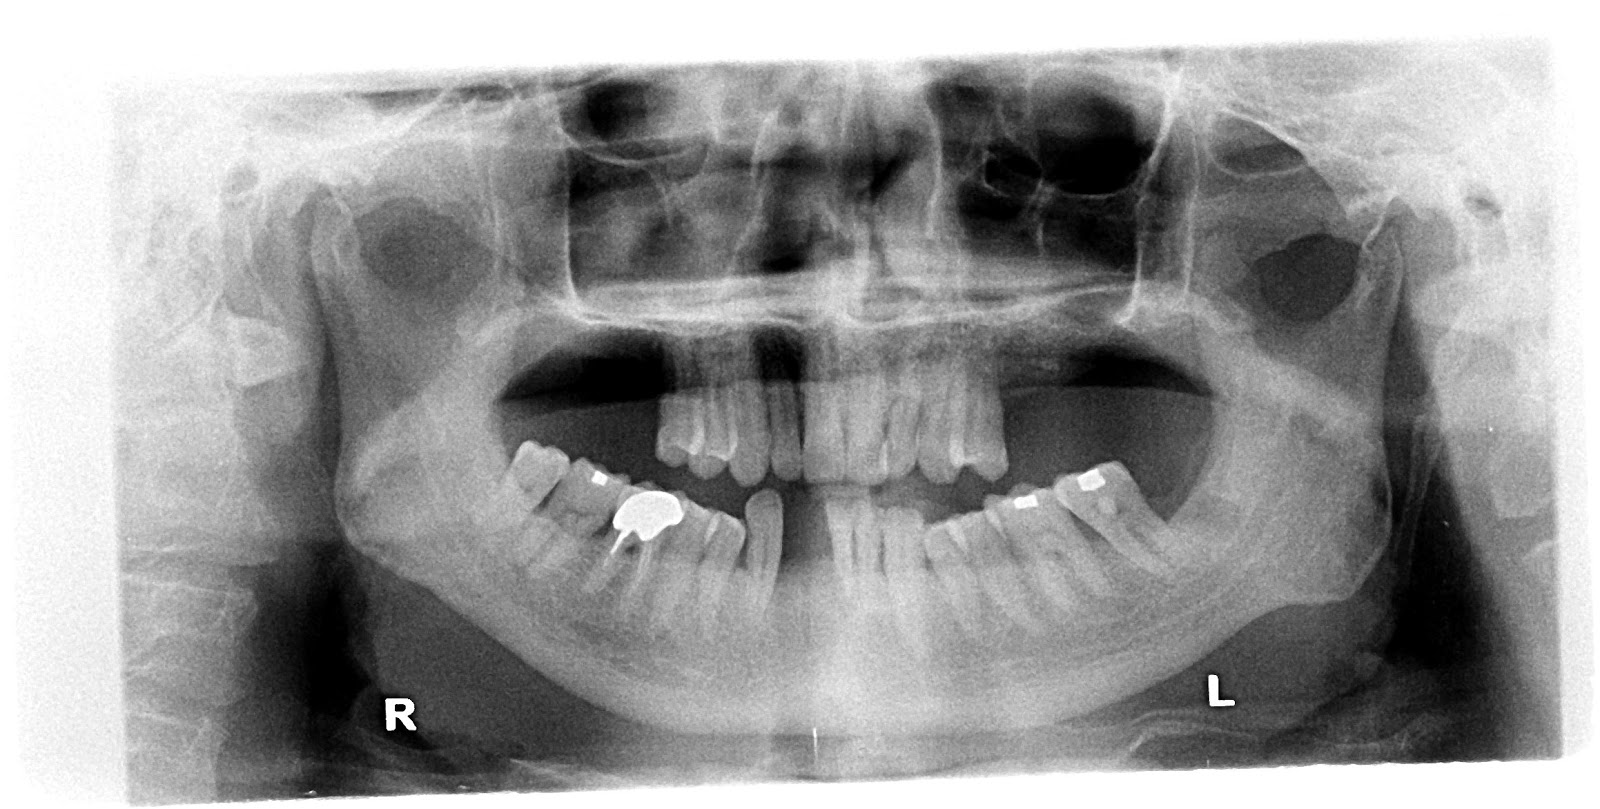

Prior to commencement of surgery, careful and detailed planning is required to identify vital structures such as the inferior alveolar nerve or the sinus, as well as the shape and dimensions of the bone to properly orient the implants for the most predictable outcome. Two-dimensional radiographs, such as orthopantomographs or periapicals are often taken prior to the surgery. Sometimes, a CT scan will also be obtained. Specialized 3D CAD/CAM computer programs may be used to plan the case.

VISTA for single upper anterior tooth + GBR

Pre-OP

Osseous defects

Bio-Oss(L) + Bio-Glide

Suturings

Final restoration(2012.07.27)

PreOP

PostOP

4 wks’ healing

6 mo healing

Post dental implantation.

Bone resorption after extraction